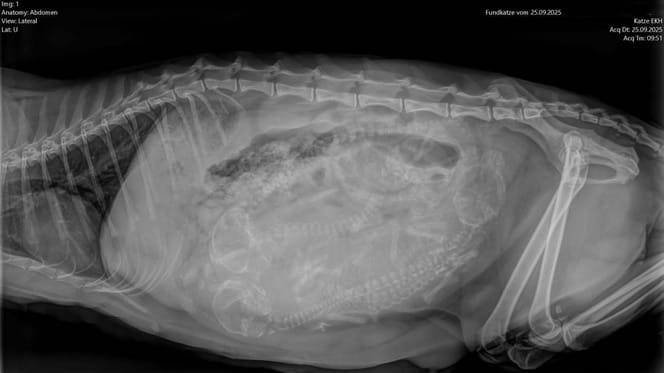

Das Röntgenbild zeigt: etwas stimmt nicht

Wie bei allen neu aufgenommenen Tieren machen die Tierpfleger eine gründliche Untersuchung. Dabei fällt etwas auf: Die Katze bewegte sich steif, als hätte sie Schmerzen. Um sicherzugehen, wird ein Röntgenbild gemacht und das Ergebnis ist niederschmetternd.

Die Knochen der Katze zeigen deutliche Deformationen – ein typisches Anzeichen der Qualzucht-Rasse Scottish Fold. Die niedlichen, nach vorn geklappten Ohren, die viele Menschen so charmant finden, sind das Resultat einer genetischen Mutation. Sie verursacht chronische Knochen- und Gelenkschäden, ein Leben lang.